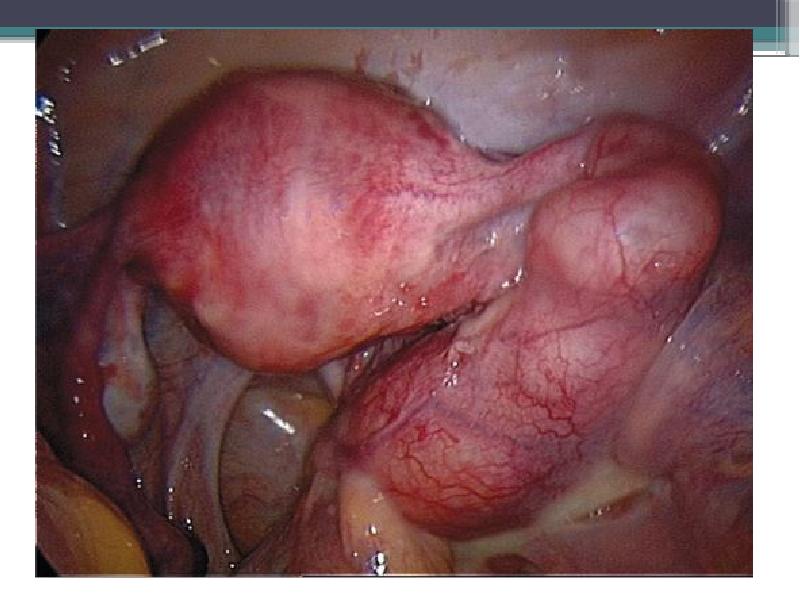

- 12. При лапароскопии возможно удаление спаек, вскрытие гнойных полостей и их дренаж.